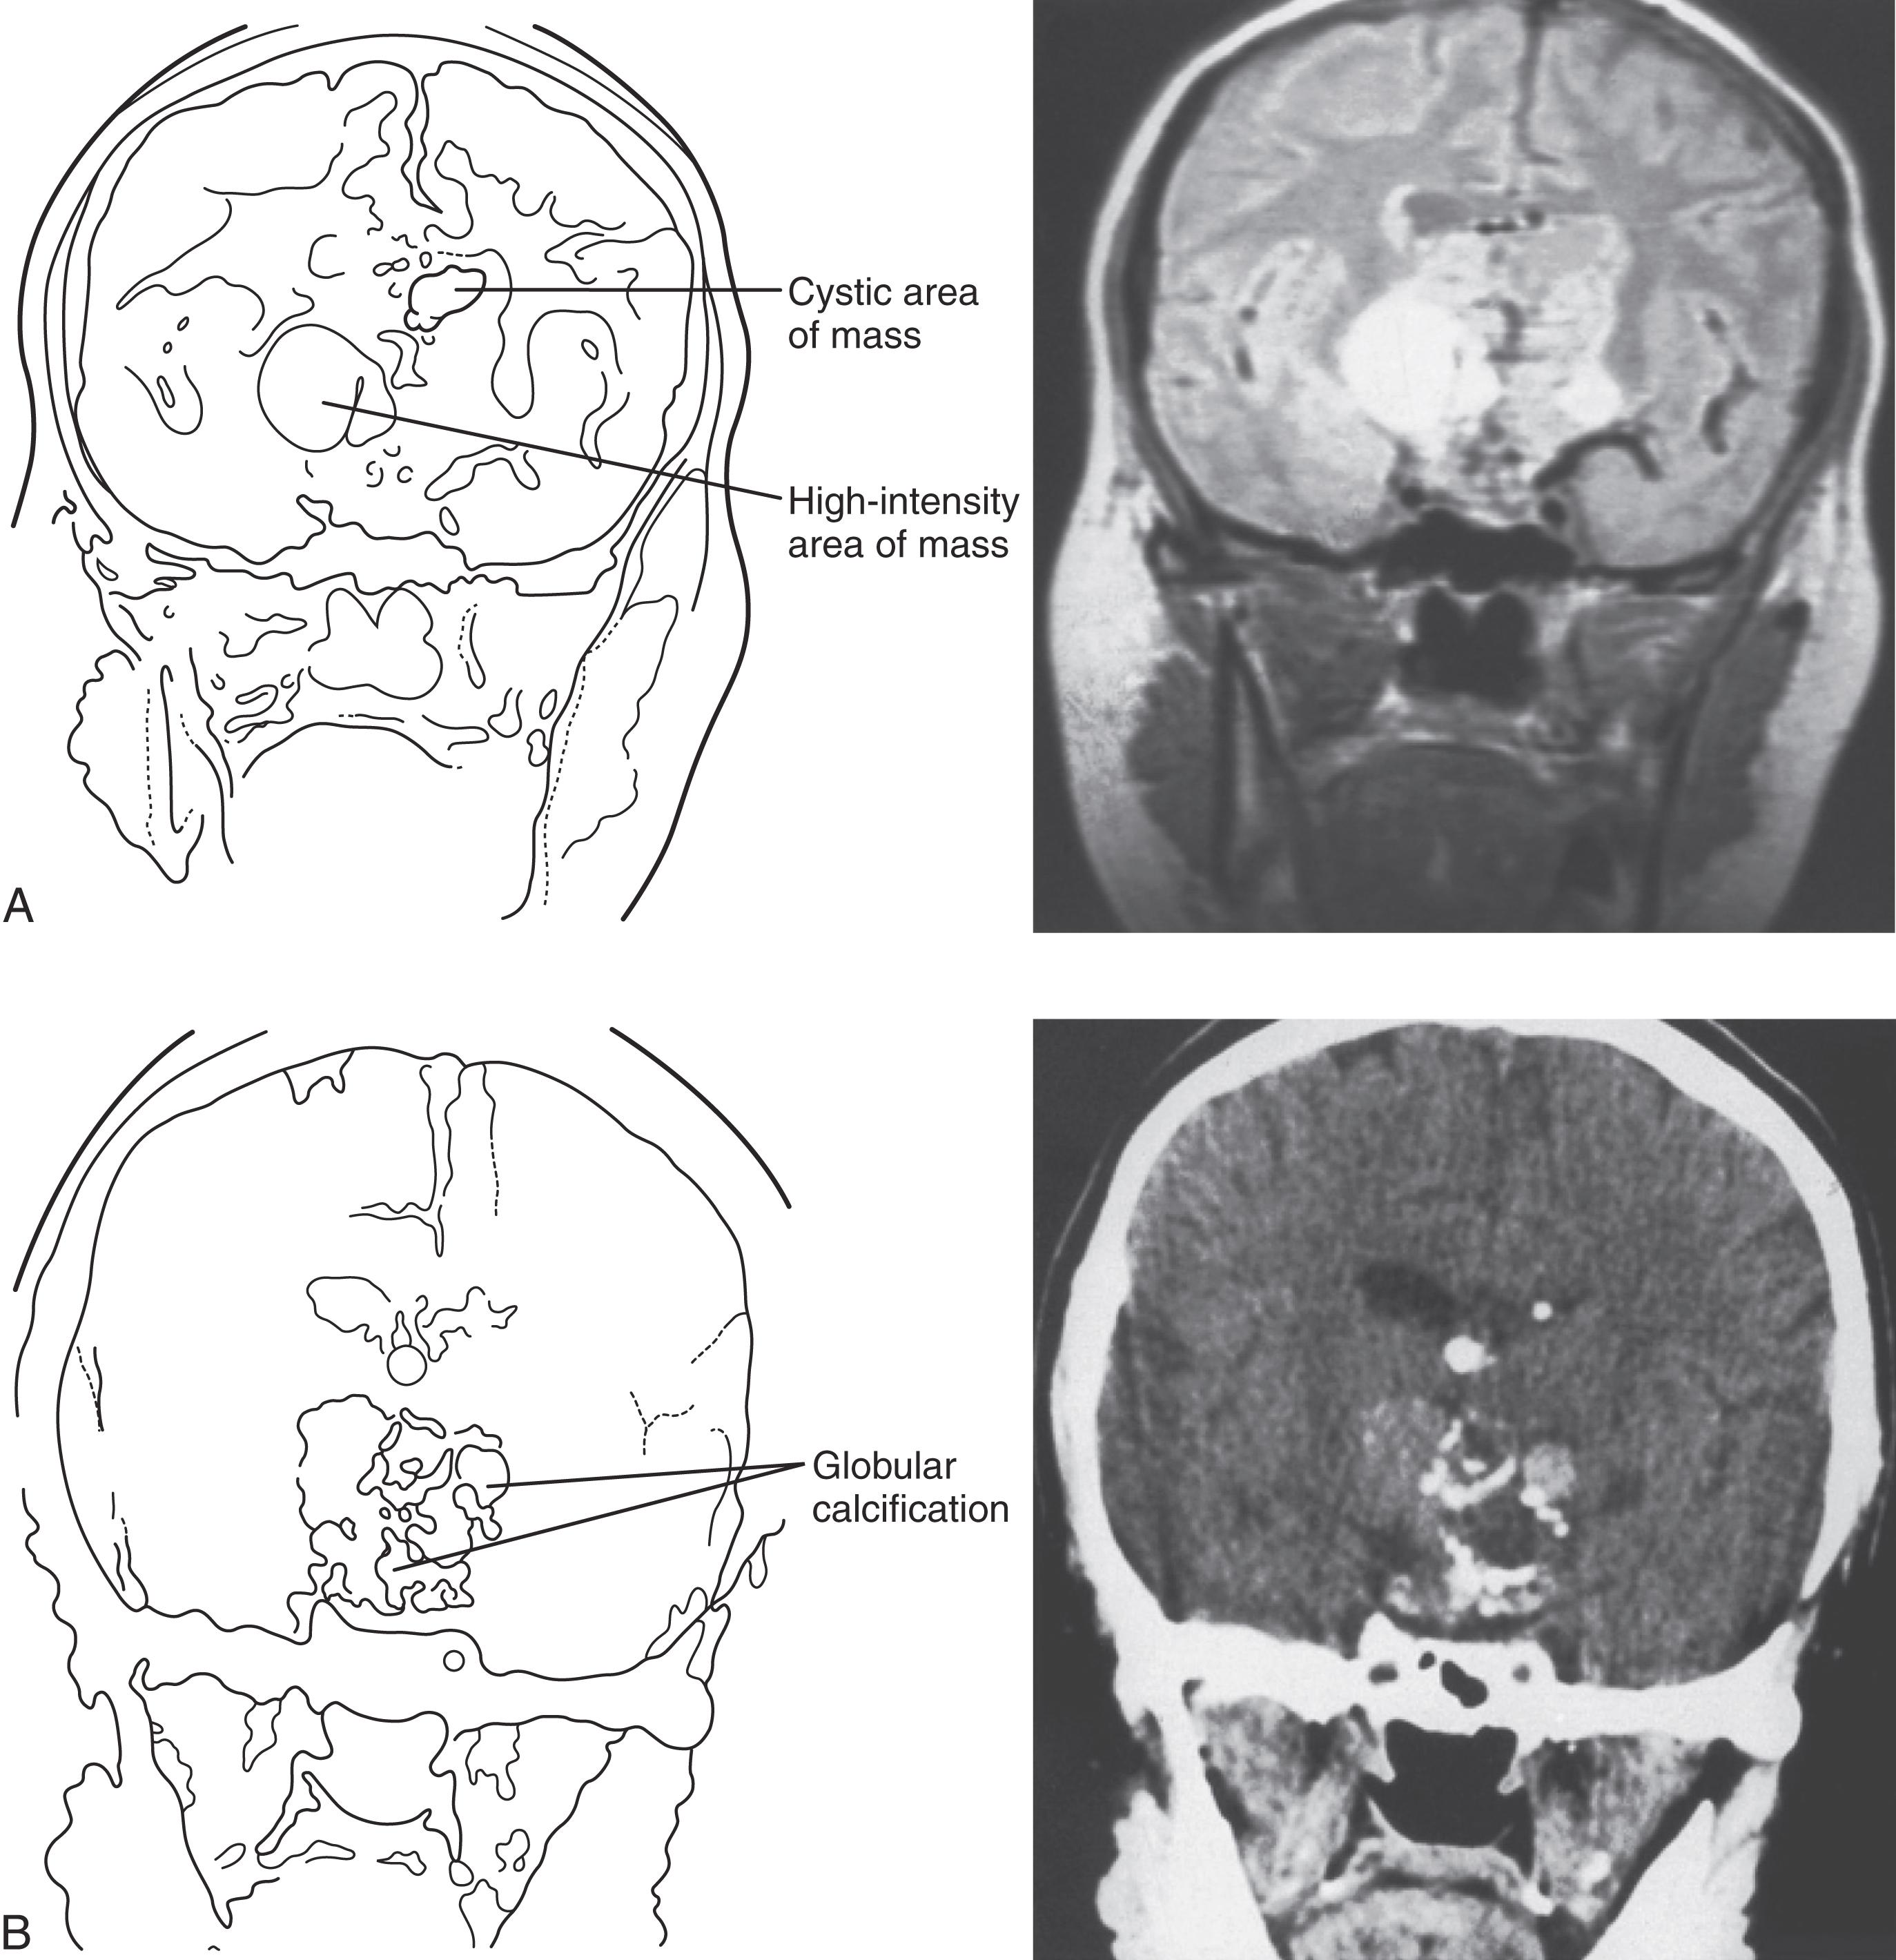

Craniopharyngiomas almost always have a suprasellar component and are rarely purely intrasellar, as shown by the images in Fig. 21.3 . Because of their proximity to vital neural structures and their significant size at the time of diagnosis (58%–76% are between 2 and 4 cm), they frequently present with headache, nausea, vomiting, visual disturbances, growth failure (in children), and hypogonadism (in adults), although the rate of tumor growth also determines the severity of symptoms. , Bitemporal hemianopsia is the most common visual complaint, occurring in almost 50% of cases. Hydrocephalus can be present, occurring more frequently in children than in adults for unclear reasons (41%–54% versus 12%–30%). With the exception of hydrocephalus and its associated symptoms, there was no difference in symptom duration or extent of hormone deficiency between children and adults with craniopharyngiomas.

Fig. 21.3, (A) Schematic and proton-density-weighted coronal magnetic resonance imaging showing a cystic area and a high-intensity signal area in a large sellar-suprasellar mass typical of craniopharyngiomas. (B) Characteristic globular calcification is apparent on a coronal computerized tomography image of the same patient.

Both computed tomography (CT) and MRI can be helpful in diagnosing craniopharyngiomas. CT can show calcification that is characteristic of the adamantinomatous subtype, whereas MRI with gadolinium enhancement provides better structural analysis. The appearance of the craniopharyngioma depends on the proportion of solid and cystic components and the content of the cyst. The solid tumor part is iso-or hypointense compared to the brain on precontrast T1 sequences and shows enhancement after contrast. On T2 sequences the signal is mixed, hypo- or hyperintense. The cystic component is hypointense on T1 and hyperintense on T2. If there is protein, cholesterol, or methemoglobin present, then there may be a high T1 and a low T2 signal. The cyst can show a peripheral contrast-enhancing rim in the T1 postcontrast images. When the findings of imaging studies are consistent with craniopharyngioma, surgical resection is usually the initial therapy, although radiation therapy (RT) has been used for small lesions not causing pressure-related visual, neurological, or endocrinological damage. The surgical approach depends on tumor size, location, degree of calcification, and the experience of the surgeon, but it often involves craniotomy and sometimes a two-stage process. Preoperative drainage of large cystic components in the days before surgery can relieve pressure-related symptoms and make surgical resection easier, although cyst cavities refill if surgery is delayed by weeks. Gross total resection is the goal in all cases, but it often cannot be achieved because of tumor size and adherence to vital neurovascular structures.